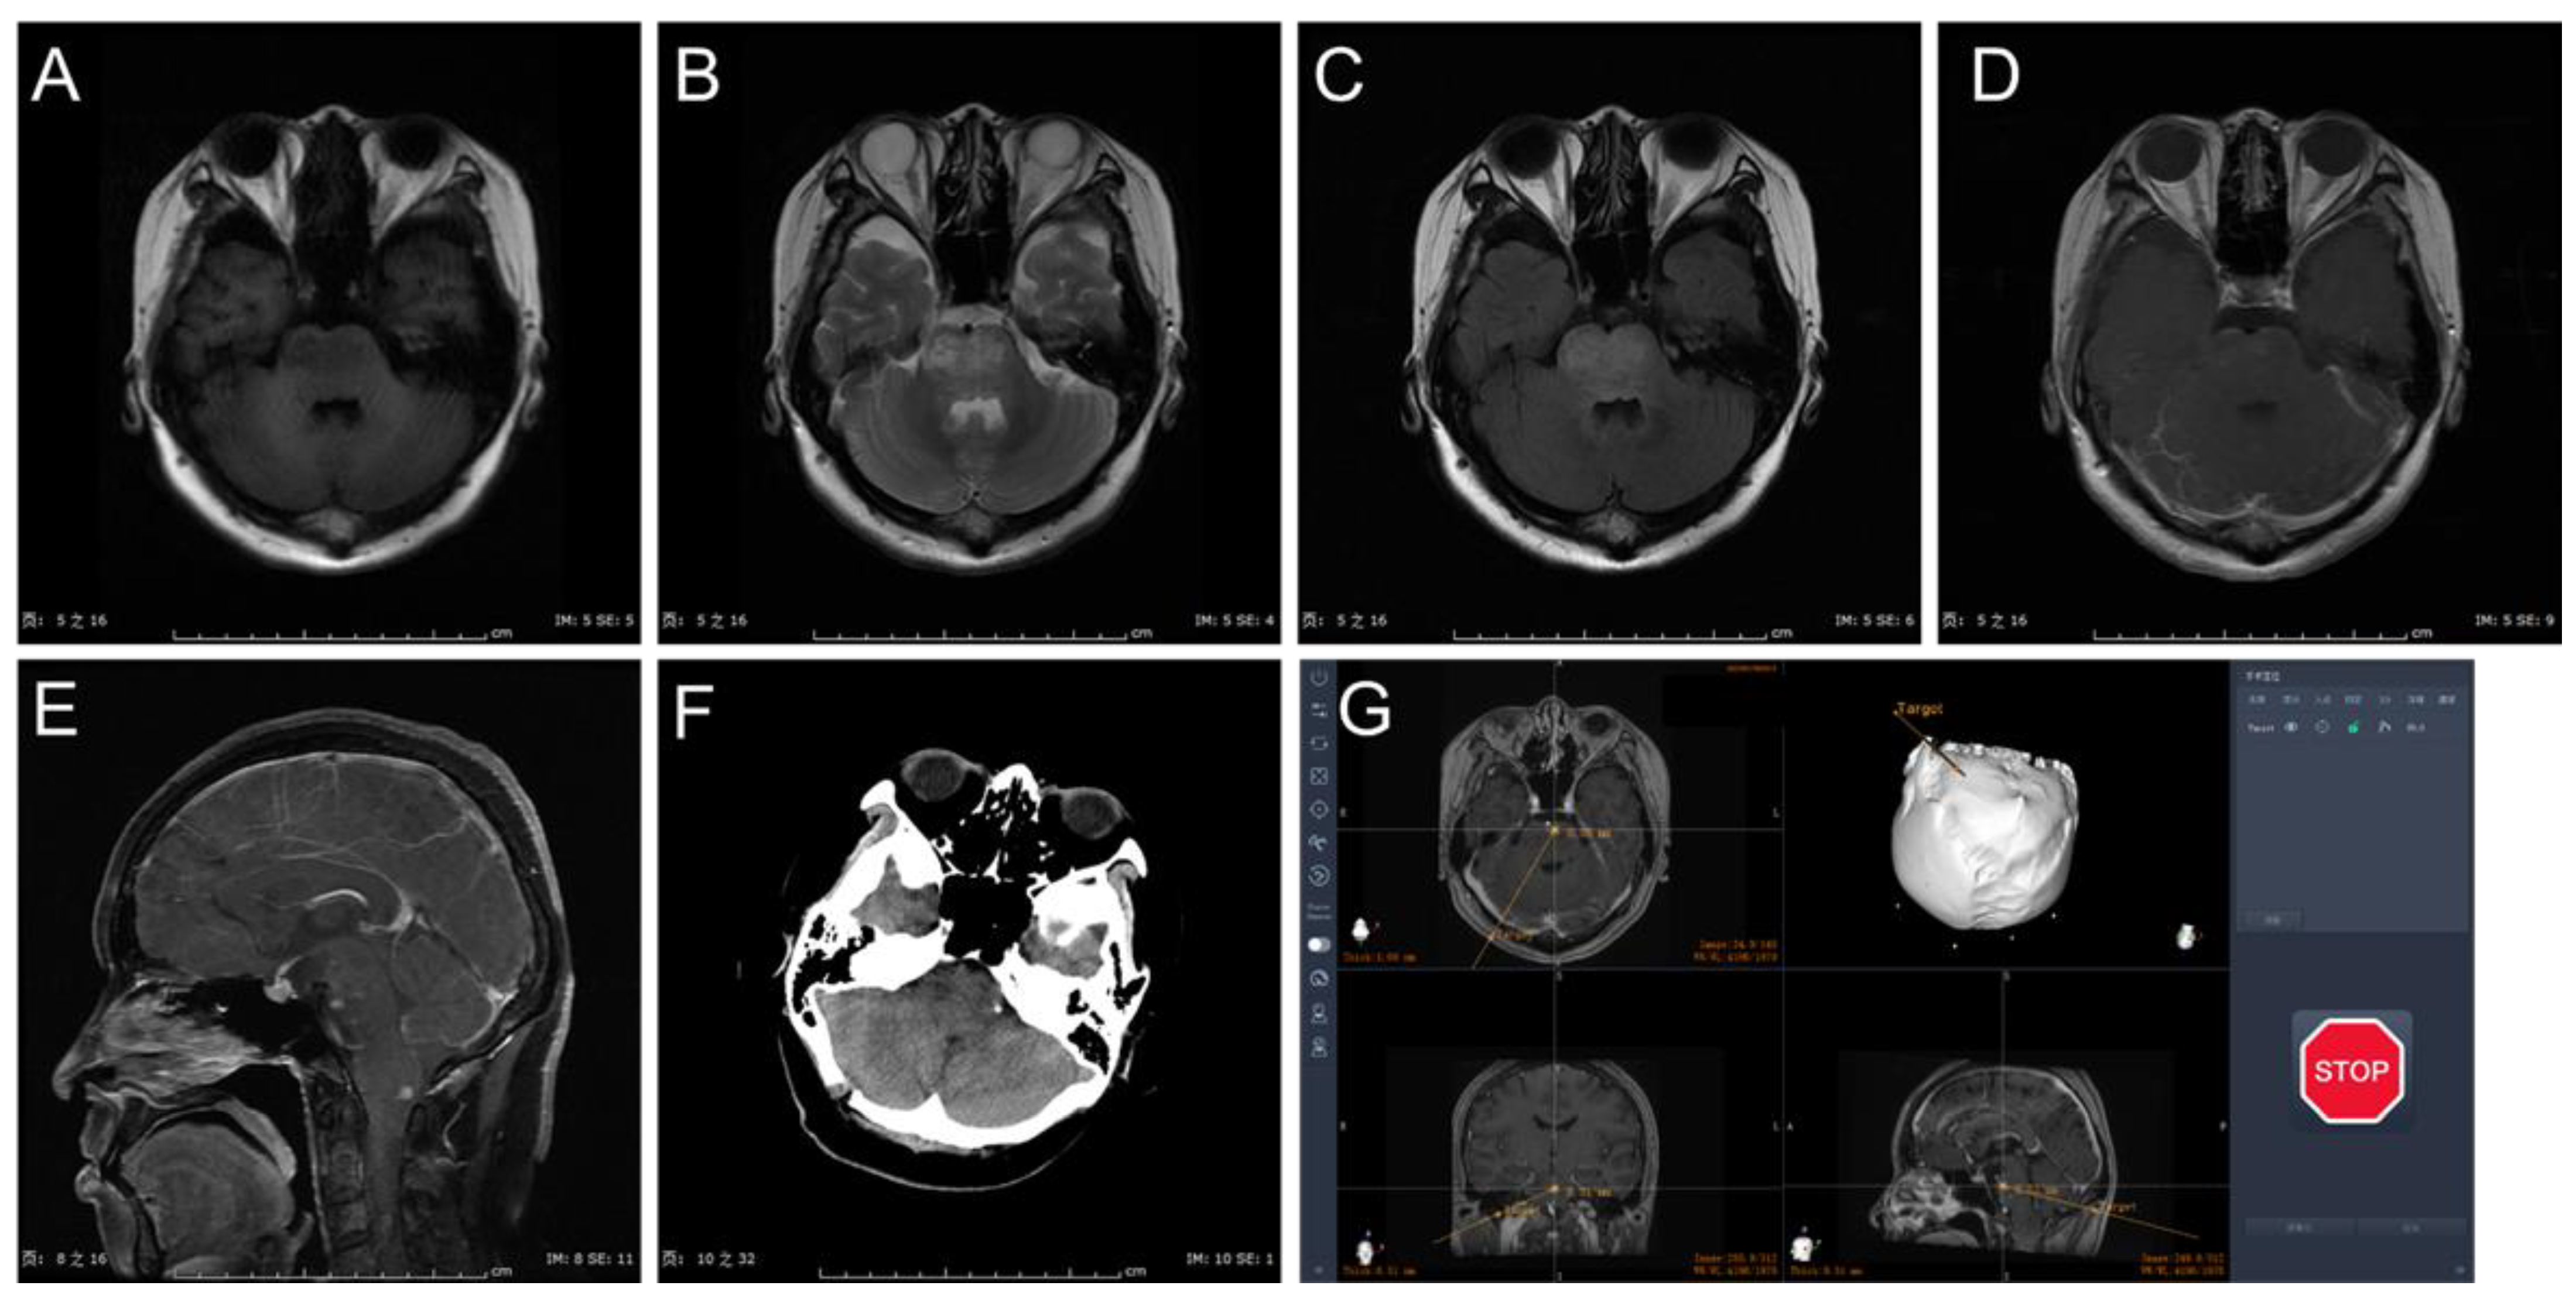

2.2. Surgical Procedure